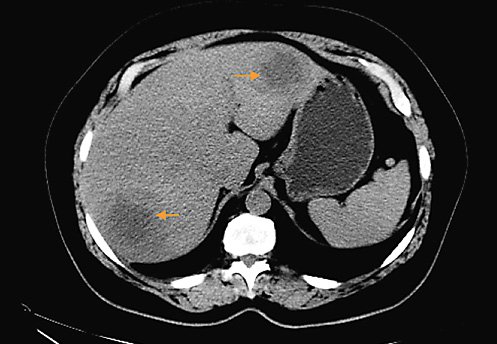

An abdominal and pelvic ultrasound was performed, which revealed three solid nodules in the liver. These were first characterized by computed tomography (CT) scan and then by magnetic resonance imaging (MRI): two in the right lobe (segment VII and V), both with about 6 cm, and one in the left lobe, with about 4.5 cm, all of them with restricted diffusion and central necrosis suggestive of secondary deposits, in a liver without stigmas of chronic liver disease. Adenomegalies and splenomegaly were excluded.

Subsequent thoracic, abdominal, and pelvic CT scan (Fig. 1) excluded other lesions, including primary lesions suggestive of neoplastic disease. A positron emission tomography scan (PET scan) was not performed. A CT-guided biopsy of the liver lesions was made, revealing a diffuse large germinal center B-cell-like lymphoma expressing CD10+, blc-6, and MUM1, without rearrangement of the MYC and BCL2 genes (Fig. 2).